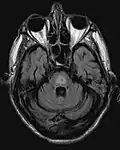

El antecedente de haber sufrido hiponatremia, sumado a las características clínicas previamente descritas son el sello de la enfermedad. La resonancia magnética puede mostrar ciertos cambios a nivel del parénquima cerebral, como es el aumento en la intensidad a nivel pontina[4]

Mielinolisis central pontina -